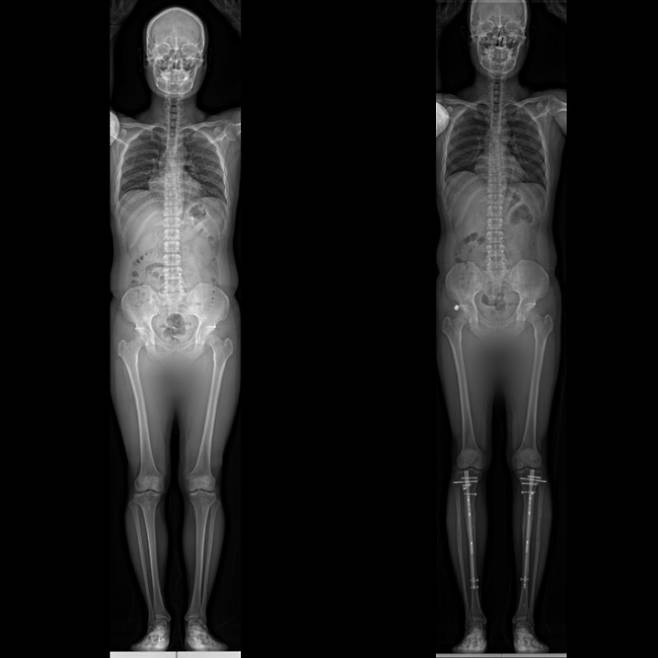

![20대 남성의 종아리와 허벅지 '골 연장수술' 전후 모습. 종아리만 연장하면 평균 6㎝, 종아리와 허벅지를 동시에 연장하면 평균 8~12㎝ 키가 커진다. [이동훈연세정형외과 제공]](https://img4.daumcdn.net/thumb/R658x0.q70/?fname=https://t1.daumcdn.net/news/202202/26/ned/20220226110154286ykex.jpg)

=사지연장술은 어떤 고정장치를 사용하냐에 따라 수술법이 나뉜다. 한국에선 외부·내부 고정장치를 같이 사용하는 하이브리드 방식(LON)을 선호하는데, 종아리만 수술할 경우 평균 6㎝ 연장할 수 있다. 종아리와 허벅지를 동시에 연장할 경우 키가 8~12㎝ 커진다.

![내고정 장치를 사용하는 ‘프리사이즈’ 수술을 한 환자의 전후 모습. 수술 후 사진(오른쪽)에서 종아리에 내고정 장치가 있는 것을 확인할 수 있다. [이동훈연세정형외과 제공]](https://img4.daumcdn.net/thumb/R658x0.q70/?fname=https://t1.daumcdn.net/news/202202/26/ned/20220226110159180drws.jpg)